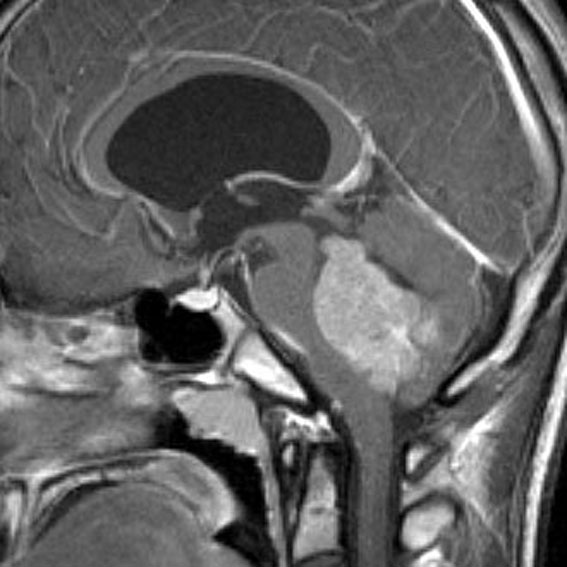

小脳虫部の毛様粘液性星細胞腫が第4脳室を閉塞して,閉塞性水頭症になっています。左の画像のように側脳室に水がたまってパンパンになっています。頭痛が生じて嘔吐しますが,ひどくなると意識障害となります。